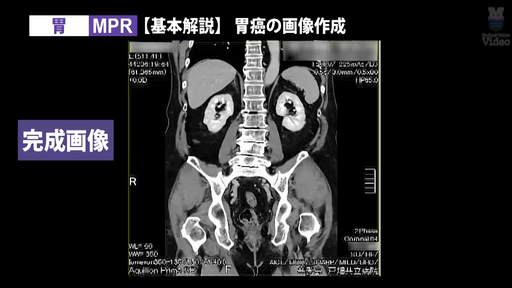

3D画像製作 胃 MPR・VR

3D画像作成の人気シリーズに、「胸郭出口症候群(TOS)」と「胃」の新作を追加。CT撮影から3D画像作成までの流れを、実際の画面キャプチャを交えて徹底解説します。

監修:山本晃義先生(戸畑共立病院)/実演・解説:田原琢朗先生

3D画像作成技術をさらに磨きたい放射線技師に向けた、実践的な内容です。